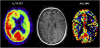

Arterial spin labeling (ASL) perfusion magnetic resonance imaging (MRI) with image acquisition at multiple inversion times is a noninvasive ASL technique able to compensate for spatial heterogeneities in transit times caused by collateral blood flow in patients with severe stenosis of the cerebropetal blood vessels. Our aim was to compare ASL-MRI and H(2)(15)O positron emission tomography (PET), the gold standard for cerebral blood flow (CBF) assessment, in patients with a symptomatic internal carotid artery (ICA) occlusion. Fourteen patients (63+/-14 years) with a symptomatic ICA occlusion underwent both ASL-MRI and H(2)(15)O PET. The ASL-MRI was performed using a pulsed STAR labeling technique at multiple inversion times within 7 days of the PET. The CBF was measured in the gray-matter of the anterior, middle and posterior cerebral artery, and white-matter. Both PET and ASL-MRI showed a significantly decreased CBF in the gray-matter of the middle cerebral artery in the hemisphere ipsilateral to the ICA occlusion. The average gray-matter CBF measured with ASL-MRI (71.8+/-4.3 mL/min/100 g) was higher (P<0.01) than measured with H(2)(15)O PET (43.1+/-1.0 mL/min/100 g). In conclusion, ASL-MRI at multiple TIs is capable of depicting areas of regions with low CBF in patients with an occlusion of the ICA, although a systematic overestimation of CBF relative to H(2)(15)O PET was noted.